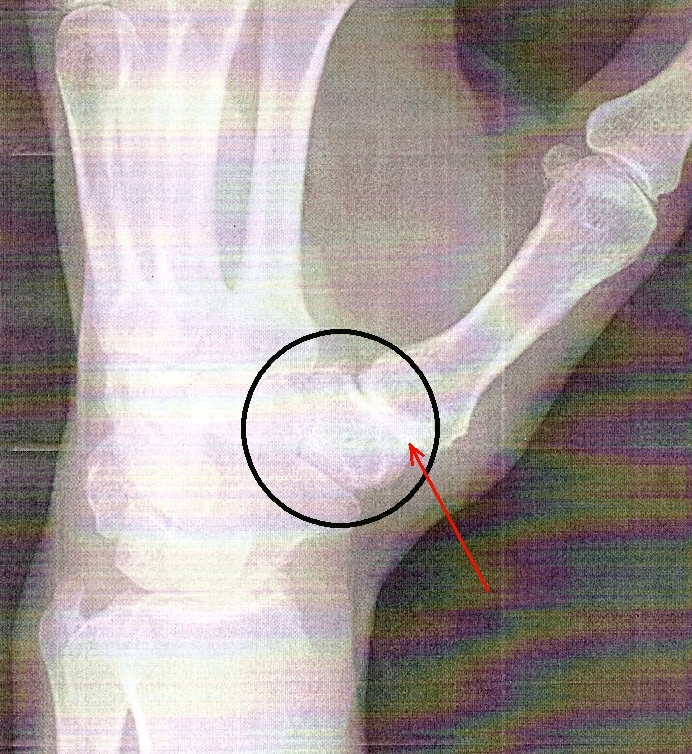

You can see the arthritis in this x-ray because there is no space between those two bones (red arrow). The cartilage that separates two bones will show up as a space between the bones in an x-ray because it isn't as dense as bone. As you can see, there's no space here. There was bone-on-bone contact. The surgery was on June 6th, 2014. |

The first cast was removed about 2 weeks after the surgery. You can see the z-shaped incision where the main work was done. The doctor also made a 2-inch incision on the bottom of my arm to harvest a piece of tendon that was used to secure the appliance. |